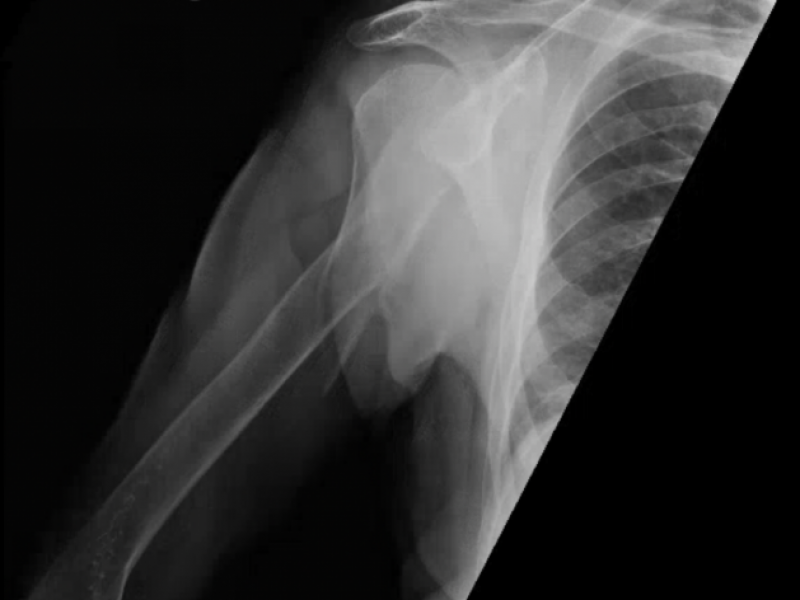

What's the Diagnosis? By Dr. Loran Hatch

70 yo F presents to the ED with right arm pain. She reports